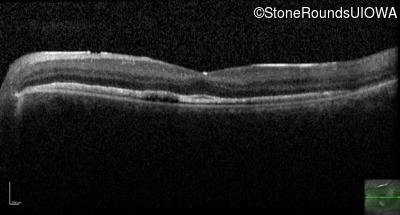

Optical Coherence Tomography - Right - 20/40 -1

Exemplar / OCT Stack

Optical Coherence Tomography - Left - 20/20 -2